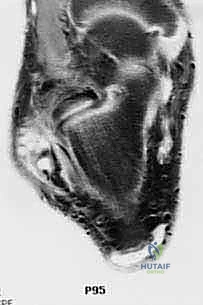

- MRI of the involved ankle: This is invaluable. It demonstrates chronic thickening, fissuring, scarring, and stenosis of the remaining peroneal structures. We'll look for tears within the tendon substance and fluid in the sheaths, which are hallmarks of chronic tendinopathy. Associated ankle pathology, such as osteochondral lesions or ligamentous instability, must also be identified.